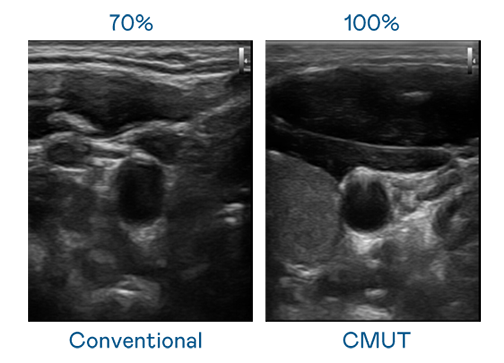

CMUT 技术是一种用电容式微机电元件来产生超音波讯号的技术。与传统 PZT 压电式技术相比,CMUT 频宽增加 30%,更宽频的超音波讯号让影像解析度大幅提升,是实现高影像品质医疗超音波扫描、促进精准医疗发展的关键技术。

大频宽带来超清晰影像

超音波影像的解析度高低,首先取决于探头能发出的讯号频宽。lehu乐虎88 CMUT 可提供高清晰的超音波讯号,提供高频宽、高灵敏度、影像纹理细节更高的超音波影像,协助医护人员缩短影像判读时间及利用精准的医疗影像进行诊断。